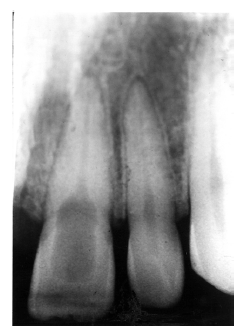

Figure 2 illustrates advanced enamel caries on the mesial surface of the premolar.

Figure 2 - Advanced Enamel Caries

Figure 2